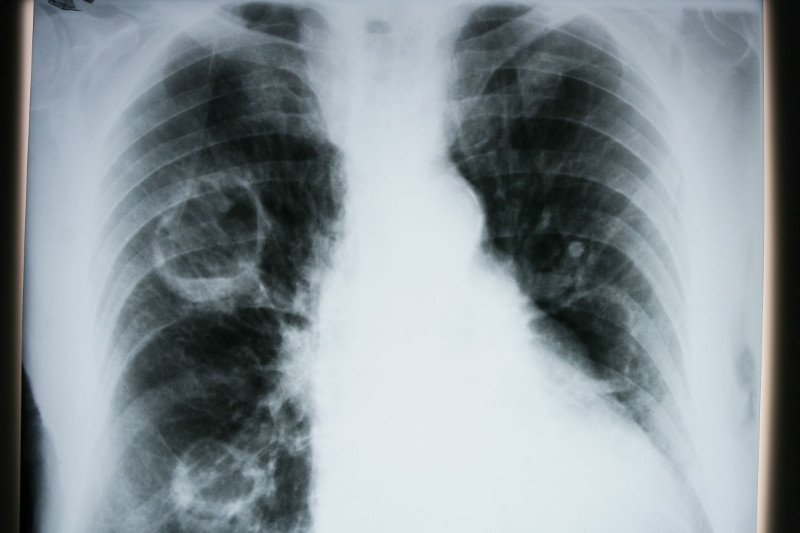

Rak płuc atakuje często, więc naukowcy ciągle szukają przyczyn oraz możliwości przeciwdziałania te tendencji. Właśnie odkryli, że istnieje związek pomiędzy występowaniem witamin z grupy B a wyższym ryzykiem zachorowania.

Epidemiolodzy z Uniwersytetu Ohio wyodrębnili czynnik, który wpływa na to, że coraz więcej ludzi choruje na raka płuc. Do tej pory uznawano, że główną przyczyną nowotworu płuc jest palenie papierosów i że to panowie znacznie częściej z tego powodu zapadają na chorobę. Oczywiście jest to prawda, bo nikotyna zwiększa ryzyko zachorowania aż o 80-90 procent. Teraz jednak wykryto pewną zaskakującą zależność.

Dr Theodor Brasky z Uniwersytetu w Ohio zauważył, że u przebadanych 32 tys. pacjentów w wieku 50-76 lat ze zdiagnozowanym rakiem, zaobserwowano wyższy poziom witaminy B6 i B12. Wynikało to zarówno z przyjmowania suplementów witaminowych, jak i spożywania produktów bogatych w te witaminy w codziennej diecie. To właśnie sprawiło, że ryzyko choroby w przypadku tych osób, u których stwierdzono podwyższony poziom tych witamin, wzrósł o 20-40 proc.

Są to dość zaskakujące dane, zważywszy, że witaminy z grupy B są dla naszego organizmu bardzo ważne. Ważne jest więc zwracanie uwagi, by nie przyjmować lub spożywać ich w nadmiarze.